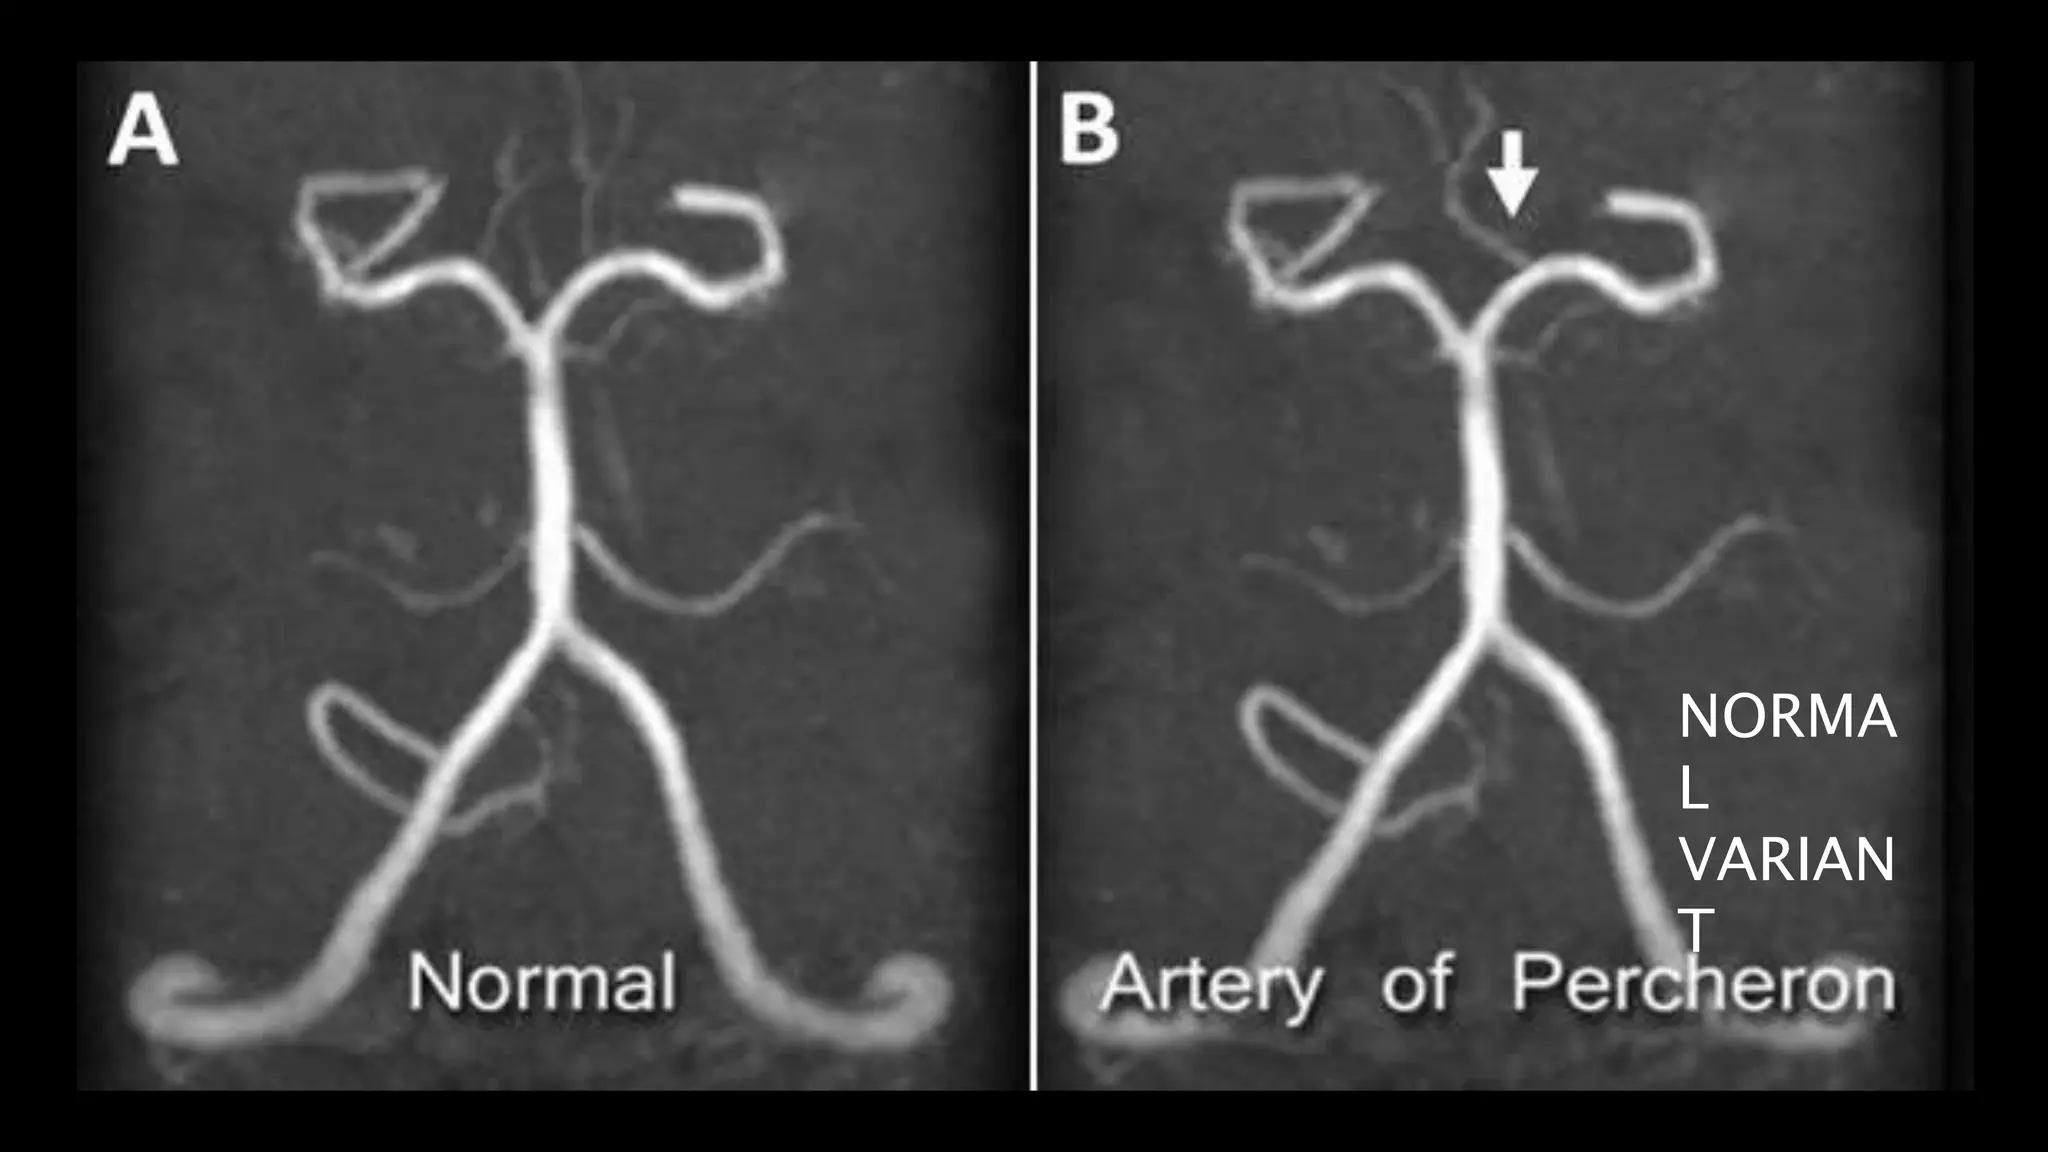

ARTERY OF PERCHERON (AOP)

INFARCTION

vascular variant

P1 PCA segment

midbrain and medial thalami

NCCT scans in early acute AOP occlusions are usually normal.

T2/ FLAIR images shows round or ovoid hyperintensities in

the medial thalami, just lateral to 3rd ventricle and midbrain.

• #156 This image shows a single dominant perforating artery fromP1 segment as compared to normal in which multiple small perforating branches supply the thamus and midbrain

• #158 This is a c/o AOP INFARCTION . Axial DWI images shows diffusion restriction in bilateral paramedian thalamic and midbrain region – consistent with acute infarct.